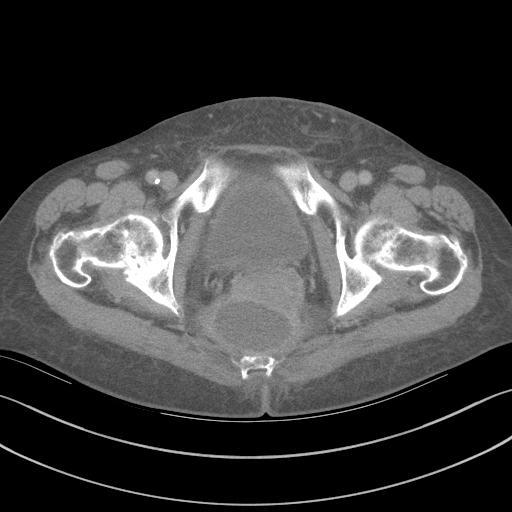

C-reactive protein and procalcitonin and other acute-phase reactant biomarkers have been studied in an effort to make an early AL diagnosis. Although there is no consensus, these biomarkers have reasonably good negative predictive value but lack positive predictive value.[10] Contrast enema and computed tomography (CT) are the most useful confirmatory diagnostic radiologic studies (Figure 1 and Figure 2). However, the diagnosis of AL at imaging is not always obvious, and there is little consensus on confirmatory findings.[1] Early postoperative CT may show an obvious leak with pneumoperitoneum or extraluminal extravasation of oral or rectal contrast. However, CT also may show rim-enhancing fluid collections or specks of free air that are equivocal for leaks.[1] Compared with contrast enema, CT has the added advantage of assessing the anastomotic defect circumferentially, detecting a contained leak, an abscess where there is no extravasation of contrast, other intra-abdominal fluid collections, an associated small bowel obstruction, and/or unrecognized bowel injuries. CT is most diagnostic when performed with intravenous, oral, and rectal contrast. One study showed that CT results with rectal contrast were associated with significantly more patients with contrast at the anastomosis compared with CT scans without rectal contrast (81.7% vs. 26.0%, p < 0.001). CT results with rectal contrast are also associated with fewer false–negative scans (4.6% vs. 18.0%, p = 0.004), less mortality (4.6% vs. 16.0%, p = 0.006), and less failure to rescue (7.9% vs. 19.5%, p = 0.048).[11] For patients with a distal rectal anastomosis, the rectal catheter for delivering contrast is often positioned by the surgeon to minimize trauma and to optimize the flow of contrast through the anastomosis. It is also an opportunity to gently palpate the anastomosis for defects. Failure to diagnose an AL may result in a chronic sinus tract and cavity with long-term sepsis or need for permanent stoma.

Figure 1. Contrast Enema Showing Anastomotic Leak

Descriptive text is not available for this image